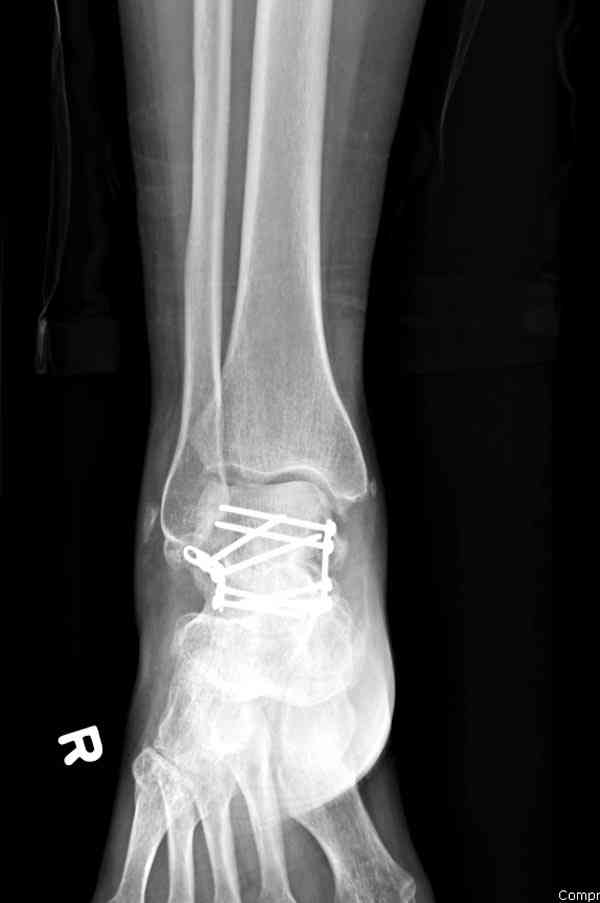

Случай с множественным оскольчатым переломом тарана оперированный из двойного доступа.

Через 2 мес.:

Через 8 мес.: